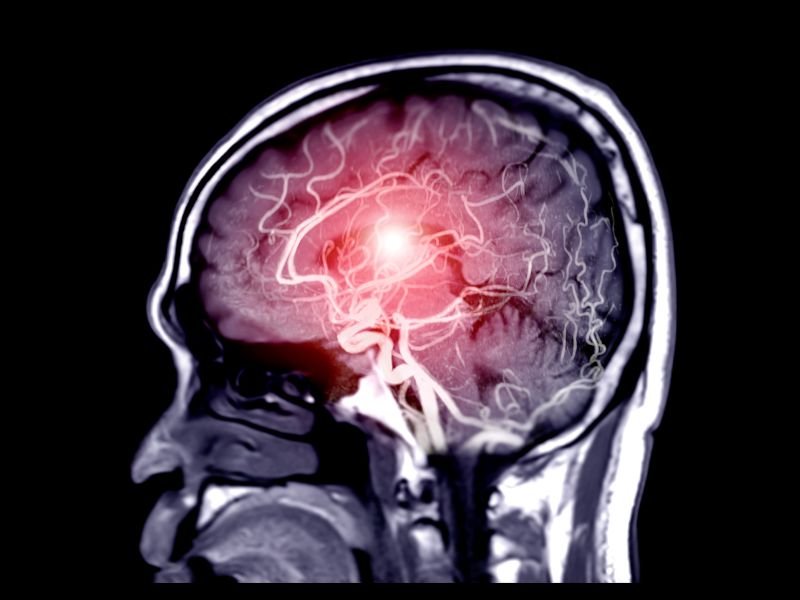

A neurocirurgia para aneurismas cerebrais é uma das áreas mais delicadas e importantes da medicina, exigindo extrema precisão, experiência e tecnologia de ponta. Em São Paulo, centros especializados como a Clínica Dr. Daniel Gil se destacam por oferecer tratamentos modernos com uma abordagem humanizada e eficaz. Com mais de 15 anos de experiência, o Dr. Daniel Gil é referência em neurocirurgia, incluindo o tratamento de aneurismas cerebrais com técnicas minimamente invasivas.

Um aneurisma cerebral é uma dilatação anormal em um vaso sanguíneo do cérebro. Essa dilatação ocorre devido ao enfraquecimento da parede da artéria, que pode se romper e causar uma hemorragia cerebral, condição conhecida como AVC hemorrágico.

Os aneurismas cerebrais podem permanecer silenciosos durante anos e serem descobertos por acaso, mas quando rompem, representam uma emergência médica com alto risco de mortalidade e sequelas.